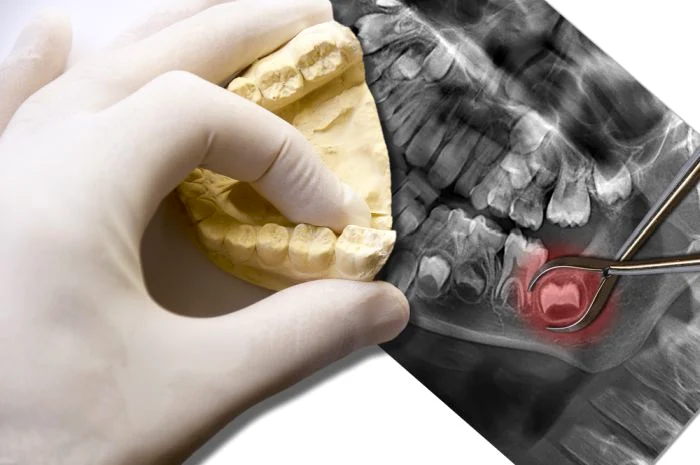

Pe lângă această cauză comună, totuşi, problemele legate de măselele de minte sunt foarte diferite şi depind de modul în care se prezintă. De foarte multe ori, acestea nu pot ieşi din gingie, care continuă să le acopere chiar şi după ce sunt complet formate. Avem de-a face cu ceea ce stomatologii numesc molarii incluşi. O măsea de minte poate fi, de asemenea, inclusă doar parţial, atunci când este doar parţial vizibilă. „Mai mult, este posibil ca aceste măsele să se dezvolte de-a lungul unei axe orizontale, mai degrabă decât a unei axe verticale. Evident, ca orice alt dinte, se poate întâmpla şi să reuşească să iasă complet şi corect.Pentru a putea avea o evoluţie normală, măseaua de minte are nevoie de spaţiu de dezvoltare pe arcada dentară matură. Cea mai problematică este, de obicei, măseaua de minte inferioară, deoarece plângerile pacienţilor sunt mai frecvente, dar şi cea superioară are complicaţiile ei.”, adaugă dr. Nassar.

În cazul în care măsele de minte nu se dezvoltă armonios şi nu sunt sănătoase, atunci acestea pot duce la dezvoltarea unor infecţii şi mai apoi la alte complicaţii, din punct de vedere stomatologic. Soluţia? Există şi este de cele mai multe oriuna chirurgicală: extracţia acestui molar.

Printr-o simplă vizită la cabinet, stomatologul sau chirurgul va verifica starea de sănătate a dinţilor şi va face recomandarea potrivită, de extracţie sau nu.